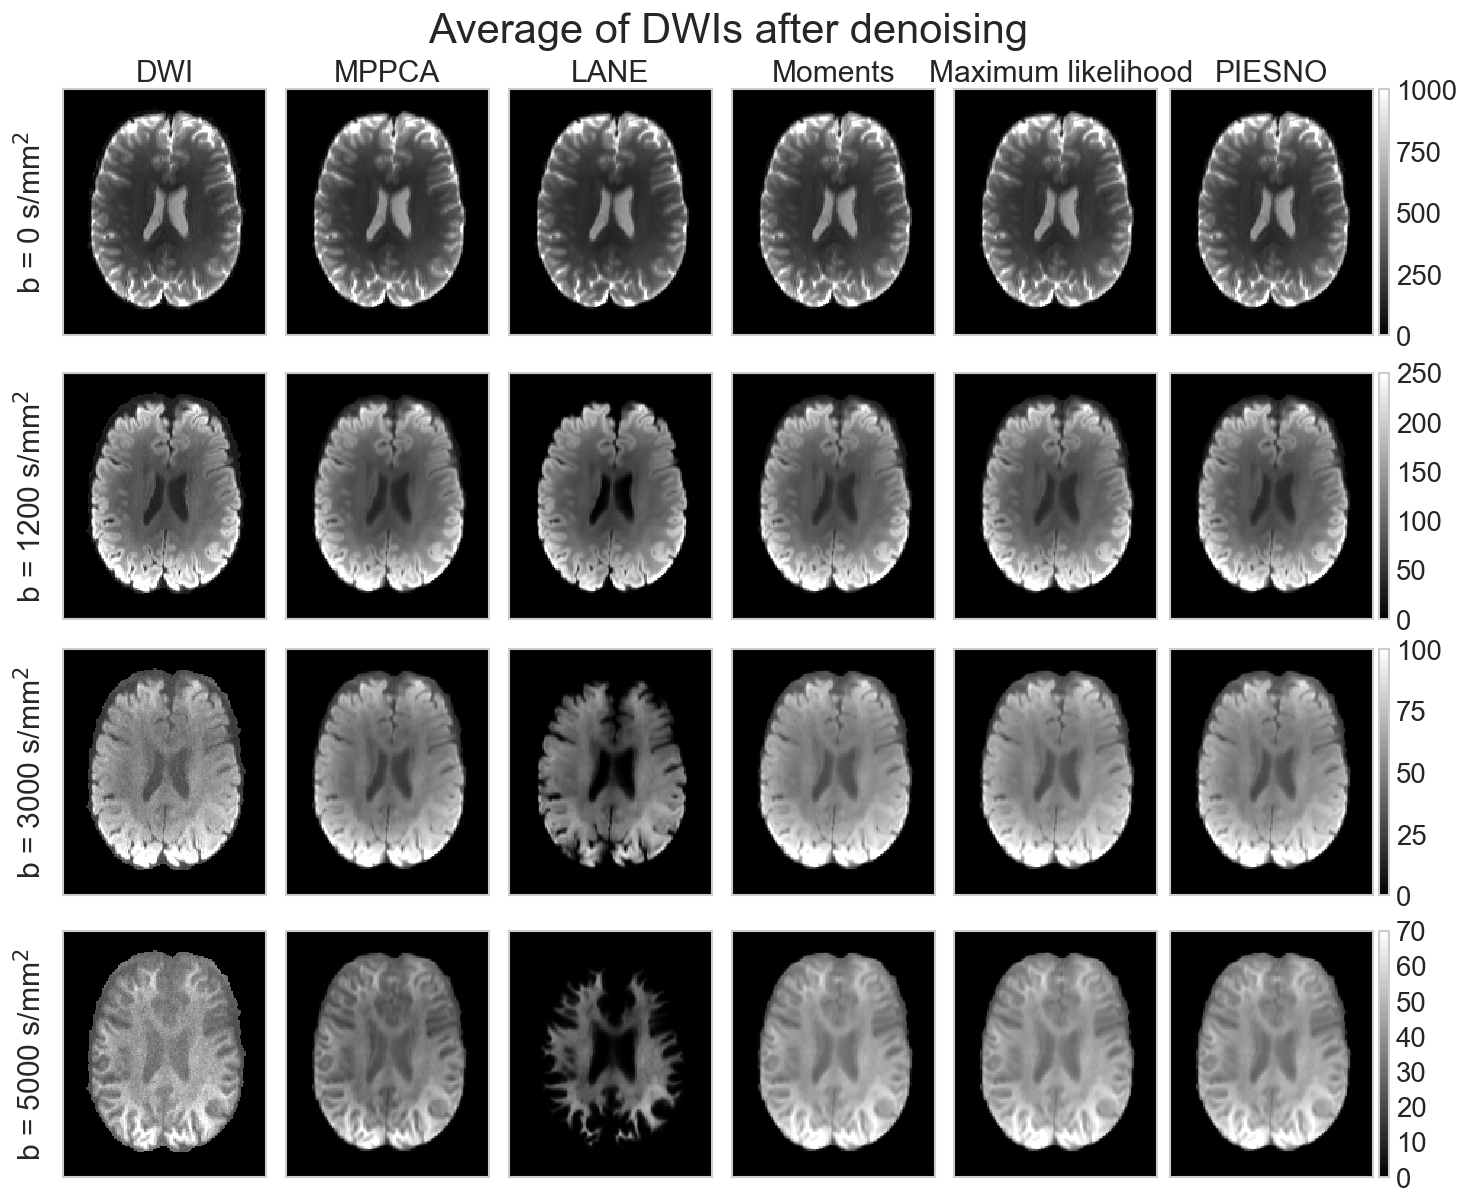

Fig. 10 shows in A) the estimated values of inside a brain mask and in B) the values of computed by the proposed methods. Estimated values of vary by an order of magnitude between the different methods. In the case of MPPCA and LANE, the median of the estimates is higher than the reference b = 5000 s/mm2 data, while PIESNO and the proposed methods estimate values lower than the reference and have lower variability in their estimated values. For the estimation of , recovered values are distributed close to 1 as is expected from an adaptive combine reconstruction providing a Rician distribution. Values estimated with the maximum likelihood equations have a lower variability than with the moments equations. In C), the top row shows the b = 5000 s/mm2 volume and spatial maps of as estimated by MPPCA and LANE. The bottom row shows voxels identified as pure noise (in light purple) using the moments, the maximum likelihood equations and PIESNO. Ghosting artifacts are excluded, but presumably affect estimation using the entire set of DWIs shown in the top row. Fig. 11 shows in A) the signal intensity after applying bias correction (left column) and after denoising (right column) for each volume ordered by increasing b-value. The top row (resp. bottom row) shows the mean (resp. standard deviation) as computed inside a white and gray matter mask. The mean signal decays with increasing b-value as expected, but the standard deviation of the signal does not follow the same trend in the cases of LANE. After denoising, the mean signal and its standard deviation decays once again as for the original data. Panel B) shows the average DWI at a given b-value for the original dataset and after denoising using the noise distribution from each method. Results are similar for all methods for the b = 0 s/mm2 datasets, but the overestimation of by LANE produces missing values in the gray matter for b = 3000 s/mm2 and b = 5000 s/mm2. In general, averaging reduces the noise present at b = 0 s/mm2 and b = 1200 s/mm2 while only denoising is effective at b = 3000 s/mm2 and b = 5000 s/mm2. At b = 5000 s/mm2, the MPPCA denoised volume is of lower intensity than when obtained by the moments, maximum likelihood equations or PIESNO. This is presumably due to LANE and MPPCA estimating higher values of than the three other methods. Finally, panel C) shows the absolute difference between the original and the denoised dataset obtained by each method. At b = 5000 s/mm2, LANE removes most of the signal in the gray matter mistakenly due to overestimating . Other methods perform comparably well on the end result, despite estimates of of different magnitude.

A)

B)

C)